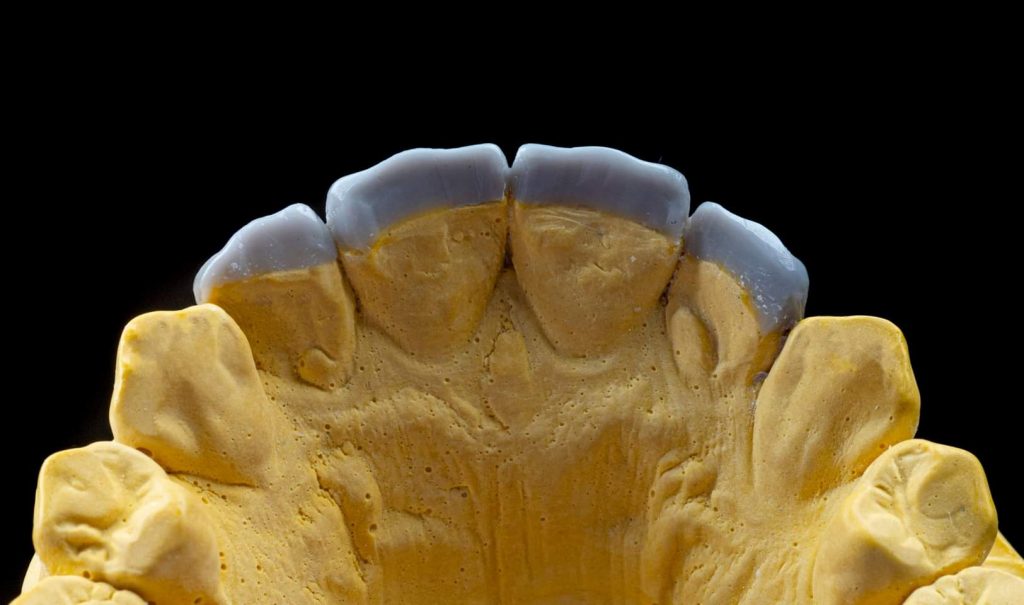

After that, anterior teeth wax-up was made according to the smile design, and in harmony with all functional movements of the mandible. Then, a silicone index was fabricated from the wax-up using vinyl polyvinylsiloxane impression materials because of their high reproduction of details and high final hardness.

Clinical note: In this case, the wax-up was made only for the central and lateral incisors. However, during the clinical procedure, I noticed that the canines were also needed some correction by composite materials to achieve better morphological shapes, and to provide better smile curve.

Finally, I would like to express my deepest gratitude to Dr. Ali Al-Qrimli ; the owner and CEO of “Digital IDEA” dental lab, with special thanks for the dental technician, Ali Kadum who did the wax-up for this case.